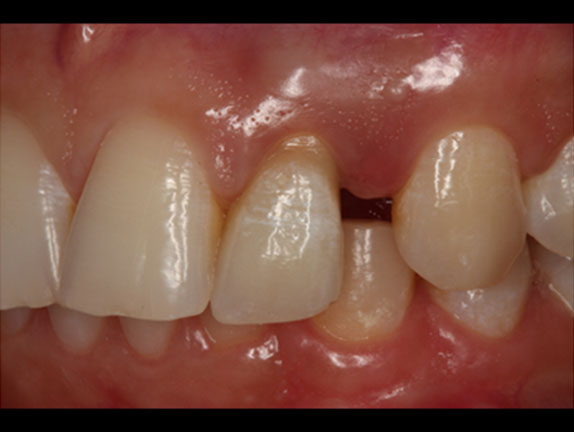

Case Report: A patient with partial edentulism, presenting absence of the upper incisors, sought an implant-supported prosthesis in the area. An absence of adequate thickness of the maxilla was observed, after a clinical and radiographic evaluation. A GBR and immediate implant installation was planned; after anesthesia and total flap detachment, two Cone Morse implants were installed in the lateral incisors area, anchored only in a coronal and apical portion, presenting exposed threads in the middle and upper area due to a vestibular bone defect. The patient’s blood was collected and centrifuged for the PRF membranes and Sticky Bone preparation by combining iPRF and lyophilized bovine bone. The implants exposed threads were covered with the Sticky Bone and the PRF membranes to assist in the process of bone regeneration and surgical wound healing. Six months after the surgical procedure, an implant-supported fixed partial prosthesis was manufactured and both implants were osseointegrated and included in the patient’s rehabilitation.